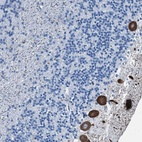

Immunohistochemical staining of human cerebellum shows strong cytoplasmic staining in Purkinje cells.